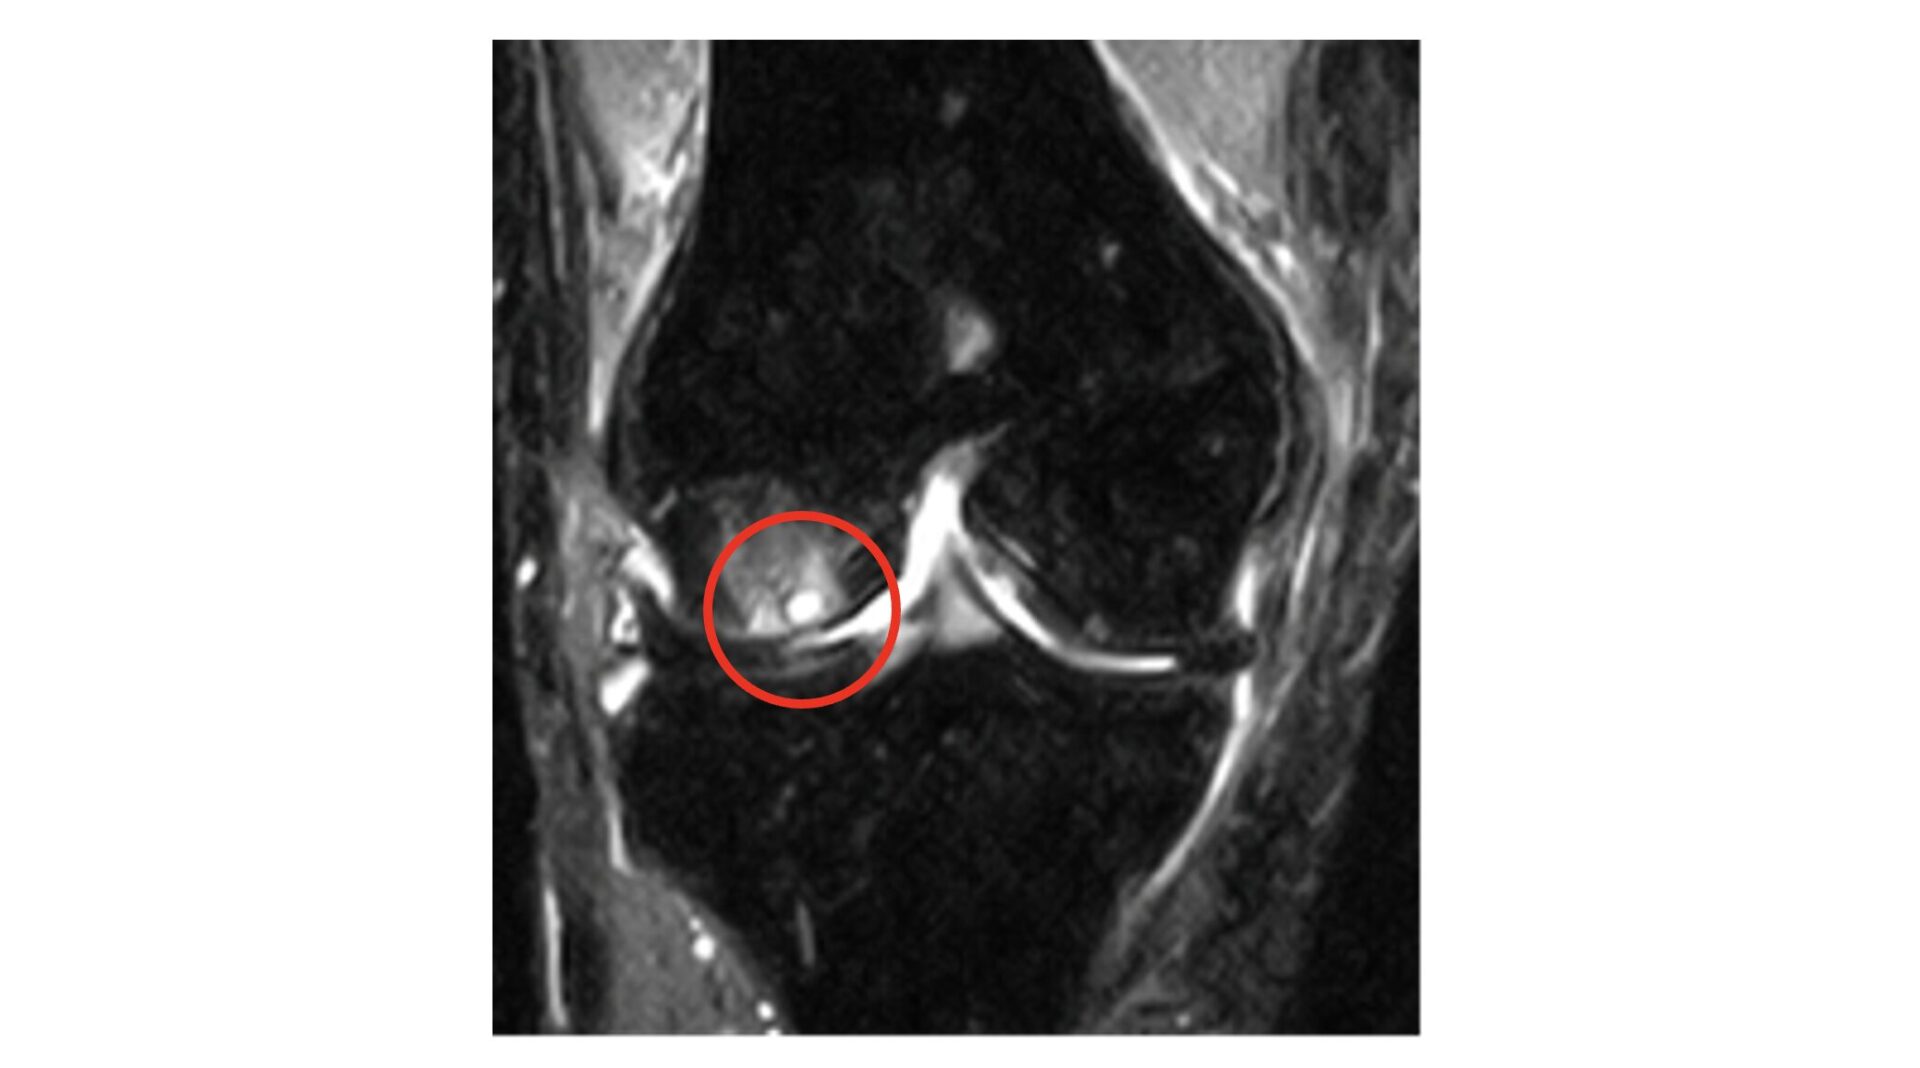

軟骨下損傷/水疱形成/骨髄浮腫

半月板損傷

MRI

軟骨・半月板・骨髄病変・滑膜まで評価でき、関節内の詳細な情報を得るのに有用です。